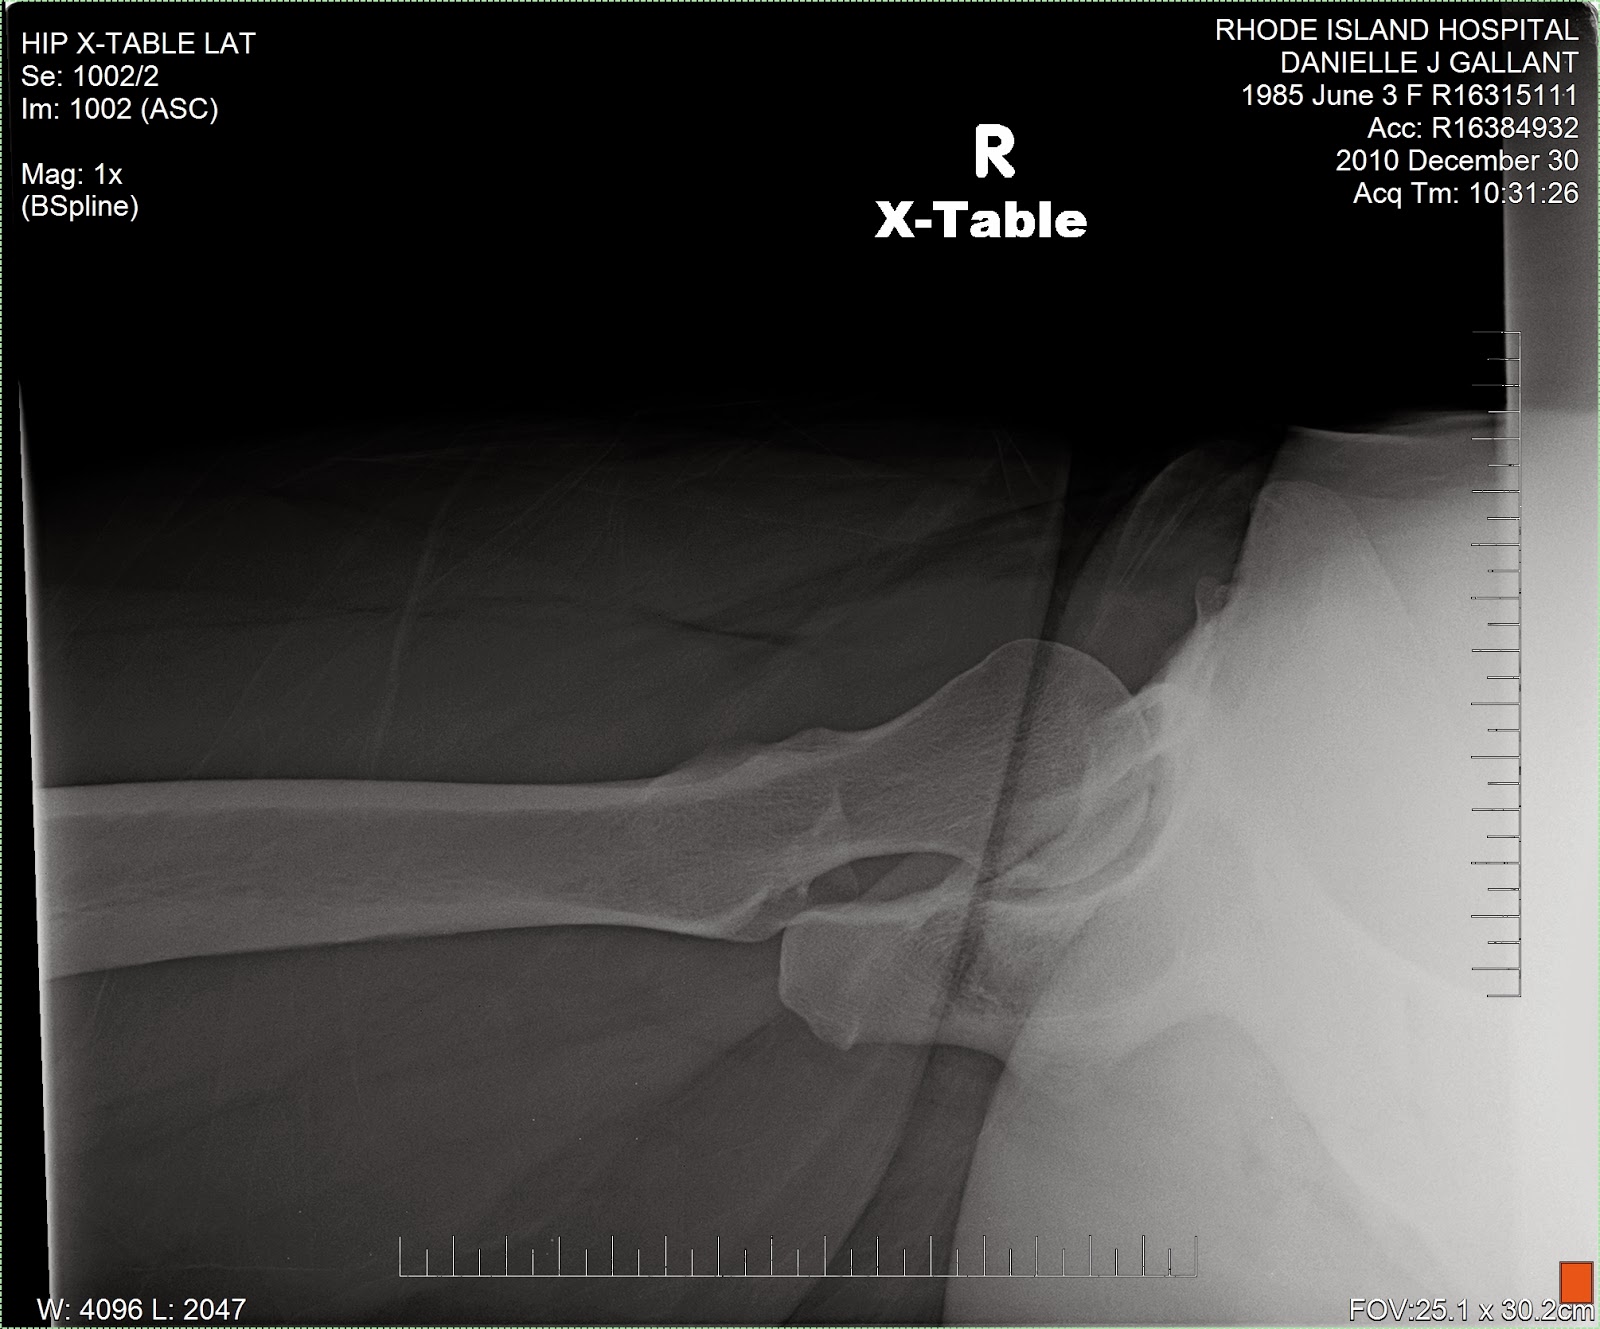

Cross Table Hip X Ray Labeled . The hip series is comprised of an anteroposterior (ap) and lateral radiograph of the hip joint. The cumulative incidence with competing risk analysis. Better demonstrates relationship of femoral head with. Begin by confirming the patient’s details, reviewing the clinical history and checking the radiographs are of the correct anatomical site (e.g. The series is requested for a myriad of. Useful in trauma patients where positioning is limited by pain. This view assesses the hip joint for any potential fractures, dislocations, bone lesions or degenerative diseases (i.e. Compare the images to previous radiographs where possible to provide additional context.

This view assesses the hip joint for any potential fractures, dislocations, bone lesions or degenerative diseases (i.e. The cumulative incidence with competing risk analysis. The series is requested for a myriad of. Useful in trauma patients where positioning is limited by pain. Better demonstrates relationship of femoral head with. The hip series is comprised of an anteroposterior (ap) and lateral radiograph of the hip joint. Begin by confirming the patient’s details, reviewing the clinical history and checking the radiographs are of the correct anatomical site (e.g. Compare the images to previous radiographs where possible to provide additional context.